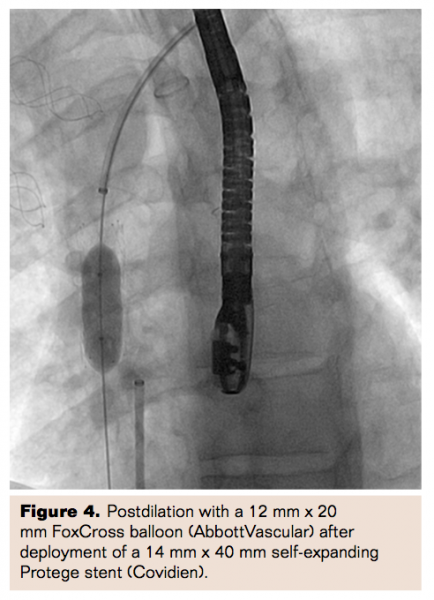

Ultimately, a 14.0 mm x 40 mm self-expanding Protege stent (Covidien) was positioned fluoroscopically across the stenosis. The stent was positioned precisely at the right atrial junction without protrusion into the atrium as confirmed by TEE (Figure 3B). After optimal positioning, the stent was deployed and postdilated with a 12.0 mm x 20 mm FoxCross balloon (Abbott Vascular) (Figure 4). Final angiography and echocardiography (Figure 5) revealed excellent stent expansion with complete resolution of the resting pressure gradient. Intra-procedural hemodynamics revealed a decrease in central venous pressure from 14 mm Hg to 6 mm Hg following stent deployment and postdilatation. Subsequently, new pacing leads were placed using the right subclavian approach. At 4 months’ follow-up, the patient was asymptomatic with complete resolution of the SVC syndrome.